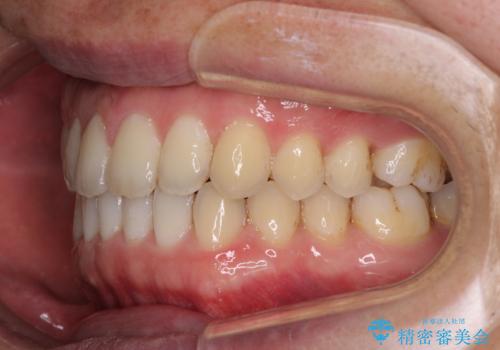

すきっ歯の改善 インビザライン矯正治療

- 上の前歯の隙間を気にして来院された患者様です。

インビザラインにより、上下の歯列を側方に拡大しつつ、前歯の隙間を閉じていくこととしました。

1日22時間の装着時間をしっかりと守ってくださったので、隙間がきれいに閉じ、口元の突出感も改善することができました。